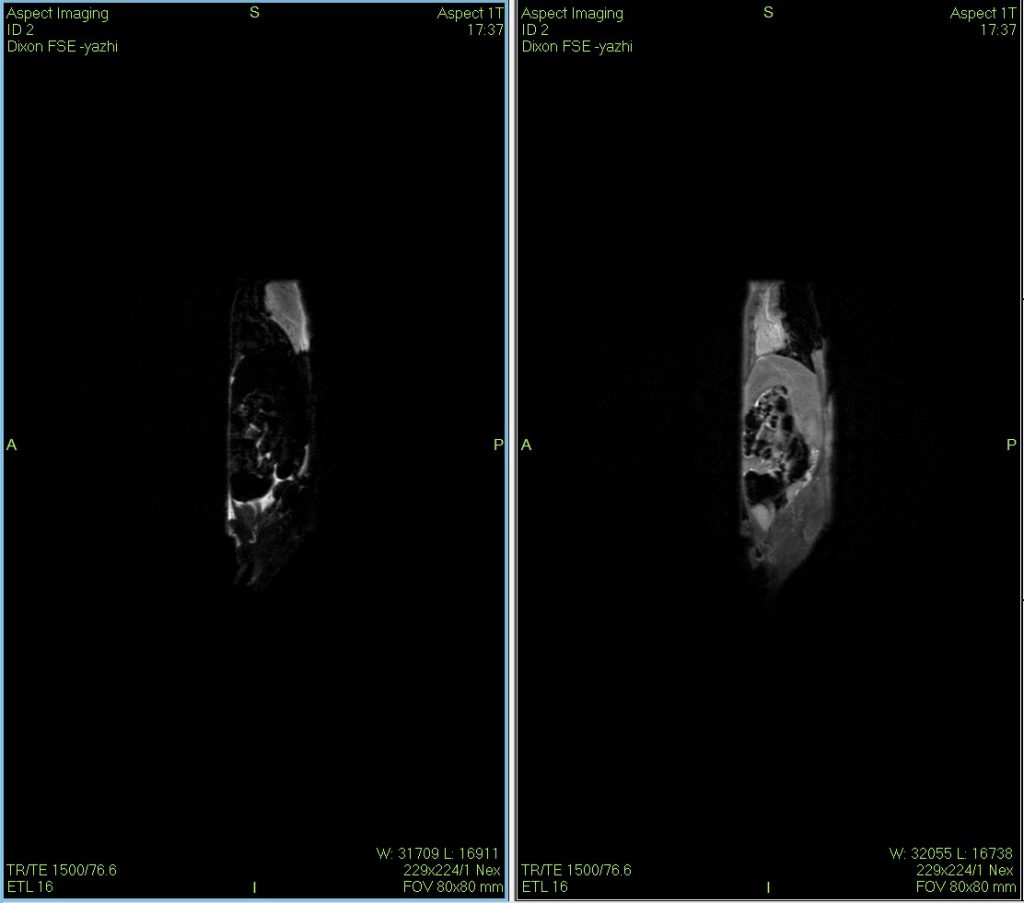

小鼠核磁共振Dixon水脂成像圖

Dixon水脂分離技術(shù)是一種使用的核磁成像技術(shù),在某些動(dòng)物疾病模型的診斷、鑒別與治療過程的評(píng)估上具有一定的獨(dú)到之處。